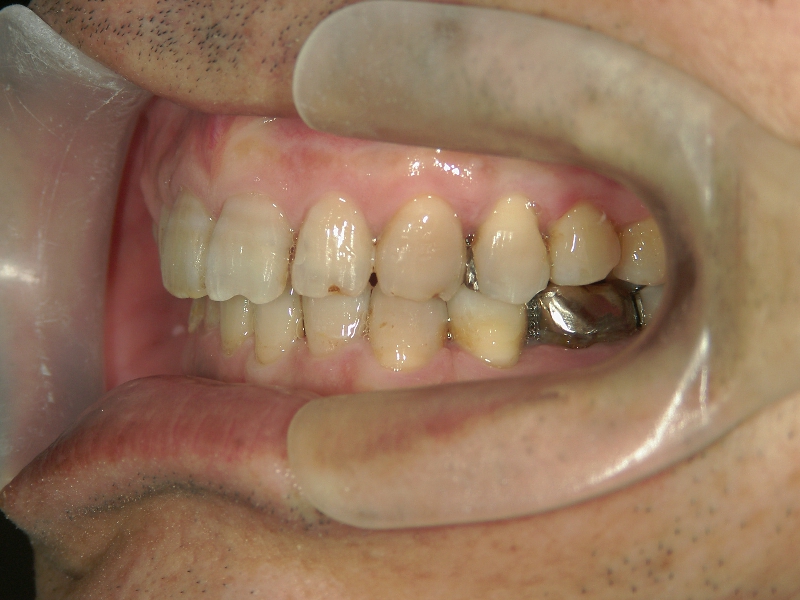

矯正歯科 治療前矯正歯科 治療前

矯正歯科 治療前 右上4番、左右下4番 計3本抜歯し、叢生を改善

no.22_8175_治療前_右.jpgno.22_8175_治療前_正面.jpgno.22_8175_治療前_左.jpg